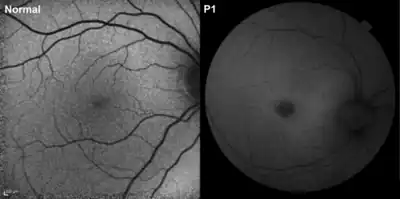

In the early infantile variant of NCL (also called INCL or Santavuori-Haltia), probands appear normal at birth, but early visual loss leading to complete retinal blindness by the age of 2 years is the first indicator of the disease; by 3 years of age, a vegetative state is reached, and by 4 years, isoelectric encephalograms confirm brain death. Late infantile variant usually manifests between 2 and 4 years of age with seizures and deterioration of vision. The maximum age before death for late infantile variant is 10–12 years.[6][7][8][9] Juvenile NCL (JNCL, Batten disease, or Spielmeyer-Vogt), with a prevalence of one in 100,000, usually arises between 4 and 10 years of age; the first symptoms include considerable vision loss due to retinal dystrophy, with seizures, psychological degeneration, and eventual death in the mid- to late 20s or 30s ensuing.[10] Adult variant NCL (ANCL or Kuf’s disease) is less understood and generally manifests milder symptoms; however, while symptoms typically appear around 30 years of age, death usually occurs 10 years later.[2]

Because vision loss is often an early sign, NCL may be first suspected during an eye exam. An eye doctor can detect a loss of cells within the eye that occurs in the three childhood forms of NCL. However, because such cell loss occurs in other eye diseases, the disorder cannot be diagnosed by this sign alone. Often, an eye specialist or other physician who suspects NCL may refer the child to a neurologist, a doctor who specializes in disease of the brain and nervous system. To diagnose NCL, the neurologist needs the patient's medical history and information from various laboratory tests.

- Electrical studies of the eyes: These tests, which include visual-evoked responses and electroretinograms, can detect various eye problems common in childhood NCLs.

All mutations resulting in the juvenile variant of NCL have been shown to occur at the CLN3 gene on 16p12;[18] of the mutations known to cause JNCL, 85% result from a 1.02-kb deletion, with a loss of amino acids 154–438, while the remaining 15% appear to result from either point or frameshift mutations.[10] The wild-type CLN3 gene codes for a protein with no known function,[4] but studies of the yeast CLN3 ortholog, the product of which is called battenin (after its apparent connections to Batten’s disease, or JNCL), have suggested that the protein may play a role in lysosomal pH homeostasis. Furthermore, recent studies have also implied the protein’s role in cathepsin D deficiency; the overexpression of the defective protein appears to have significant effects on cathepsin D processing, with implications suggesting that accumulation of ATP synthase subunit C would result.[24] Only recently have studies of human patients shown deficiency of lysosomal aspartyl proteinase cathepsin D.